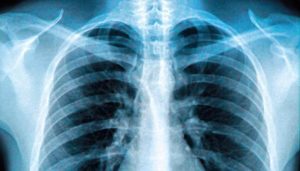

При проведении рентгена грудной клетки доктора, прежде всего, просматривают состояние корней легких. Это так называемы «врата» в главный орган дыхания. Если никаких проблем с ними нет, то на снимке они будут в нормальном состоянии, без уплотнений. Большое значение имеет и расположение корней.

Они делятся на три части: верхний, средний и нижний сектор. Правый корень по форме напоминает кривую ленту, сужающуюся книзу, он слабо выражен на снимках. Его верхняя часть находится на уровне второго межрёберья. Вершина левого корня находится на одно ребро выше, чем правый. Сам корень частично скрывает тень от сердца.

В первую очередь врачи обращают внимание на корни лёгких — структуры, которые являются так называемыми воротами в лёгкие.

В норме на рентгенограмме они не увеличены, на их фоне не видны никакие образования. Само расположение корней также имеет значение.

Корни делят на три сектора — верхний, средний и нижний. Правый корень напоминает искривлённую ленту, которая средне выражена и сужается книзу.

Верхняя часть этого корня расположена на том же уровне, что и передний отрезок второго ребра — второго межрёберья. Верхняя часть левого корня расположена на одно ребро выше правого, а сам он частично скрыт тенью от сердца.

Ширина артериального ствола корней, в большинстве случаев, не превышает 15 миллиметров.

Сами корни подразделяются на магистральные и рассыпчатые. Первый вид предполагает большую верхнюю часть (головку), которая в основном представлена лёгочной артерией. Рассыпчатые же корни обладают большой разветвлённой сетью сосудов, которые переходят в тяжи.